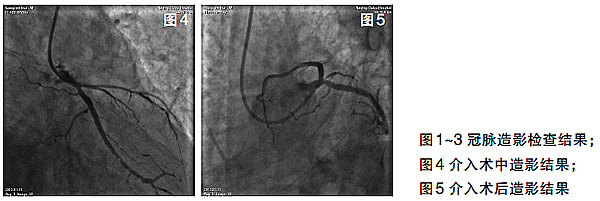

治疗经过 采用单指引导管技术(6F EBU3.5),在1.8F Finecross微导管支持下,将Fielder 300导丝通过LCX远段心外膜侧支送入LAD近段,导丝逆向穿过LAD开口闭塞病变最终送入EBU指引导管内(图4)。在逆向导丝的路标引导下,操控正向PILOT 150导丝穿透闭塞病变进入LAD远段。后沿正向PILOT 150导丝,使用1.5 mm×15 mm Sprinter球囊和2.0 mm×20 mm Voyager球囊预扩张病变,最后置入3.0 mm×28 mm 和3.0 mm×15 mm Xience Ⅴ药物洗脱支架两枚。LAD血流恢复TIMI 3级,无明显残余狭窄(图5)。